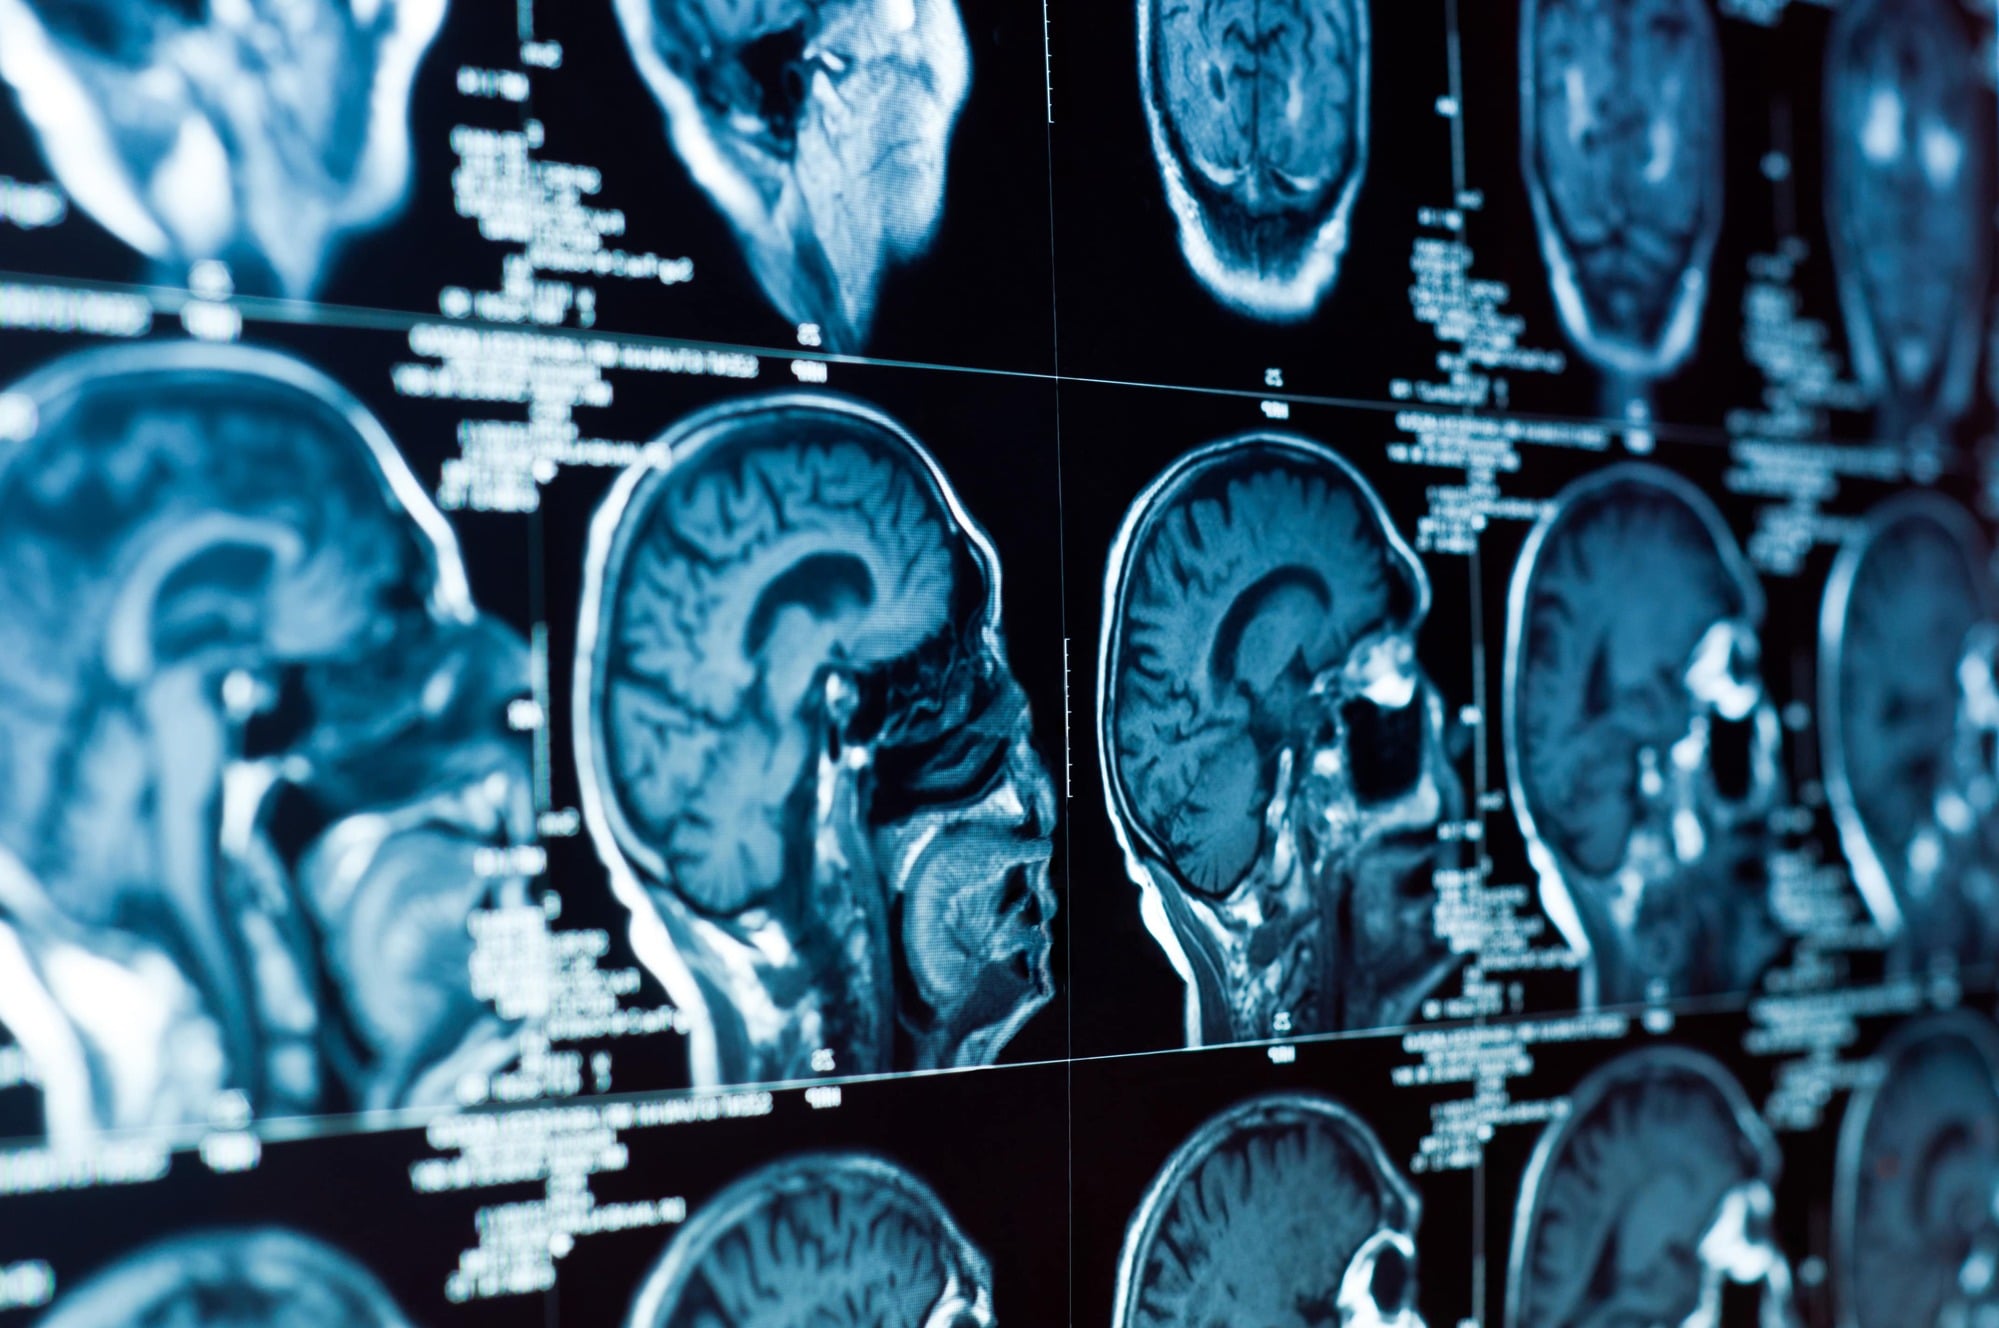

- Restricted Access to Records or Imaging: Security protocols or cost concerns limit access to CT scans or MRIs, making diagnosis difficult.